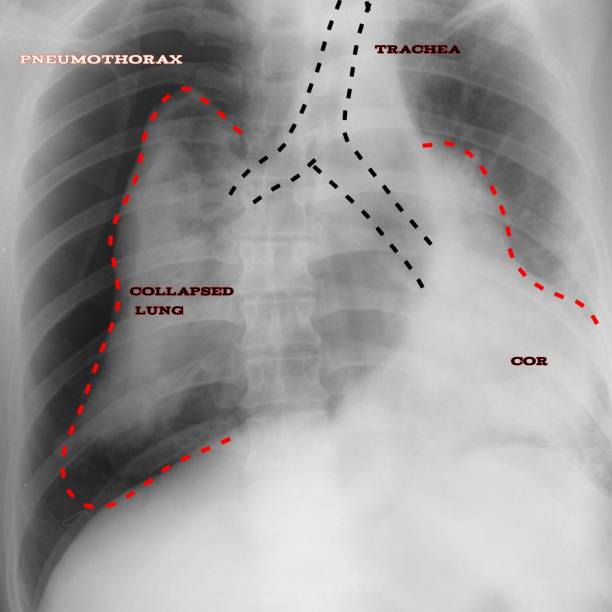

흉부 X선 검사

기흉이 의심되는 환자에게는 흉부 X선 검사를 실시하여 기흉이 있는지 확인할 수 있습니다. 이 방법은 비교적 쉽고 빠르게 기흉을 진단할 수 있습니다.